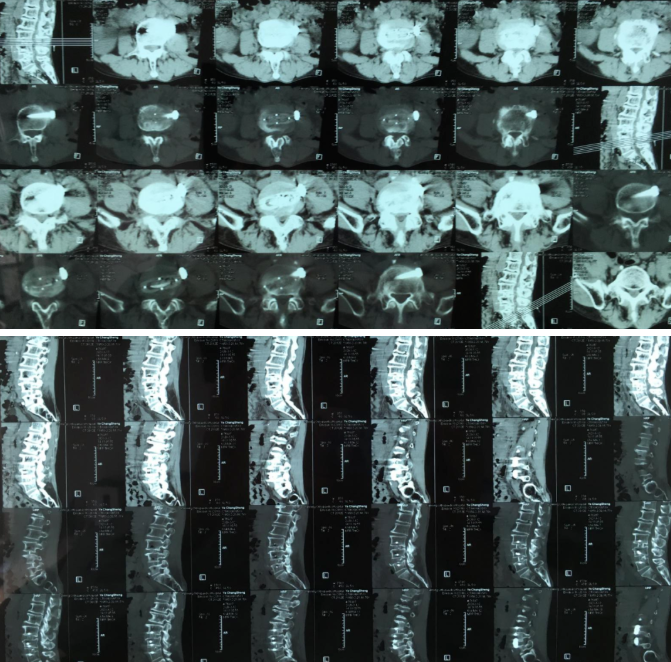

2021年7月2日-4日,中国医师协会第三届显微外科医师年会在宁波举行。我院医疗院长桃春辉当选本届全国委员,会上代表医院报告我院开展的显微镜下脊柱微创OLIF技术,受到了与会专家们关注。

“OLIF作为一种更加微创的椎间融合术,近几年在国内各大医院逐渐开展,获得越来越多临床医生的认可”桃春辉院长介绍,该手术经左下腹腹外斜肌、腹内斜肌、腹横肌的肌间隙进入腹膜外间隙,在左侧腰大肌和腹主动脉之间安放工作通道,可通过大血管间隙及腰大肌间入路进行手术,可明显减少手术创伤、缩短手术时间、减少术中出血、缩短住院时间及患者康复时间。